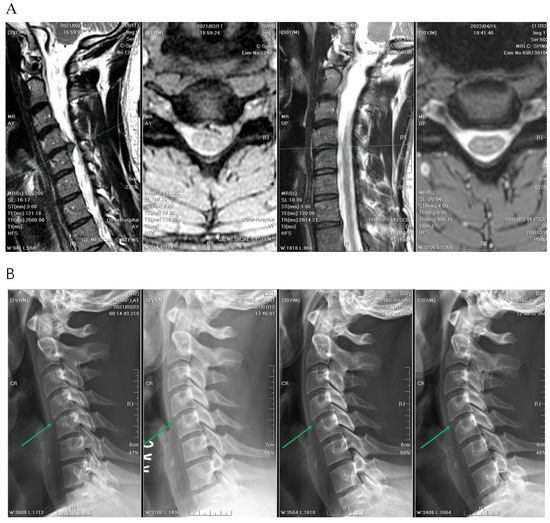

2. Materials and Methods

2.1. Patient Information

2.2. Patient Selection

2.3. Clinical and Radiological Parameters

2.4. Preoperative Workup, Positioning, and Operative Technique

2.5. APECD

2.6. PPECD

3.4. Radiographic Outcomes